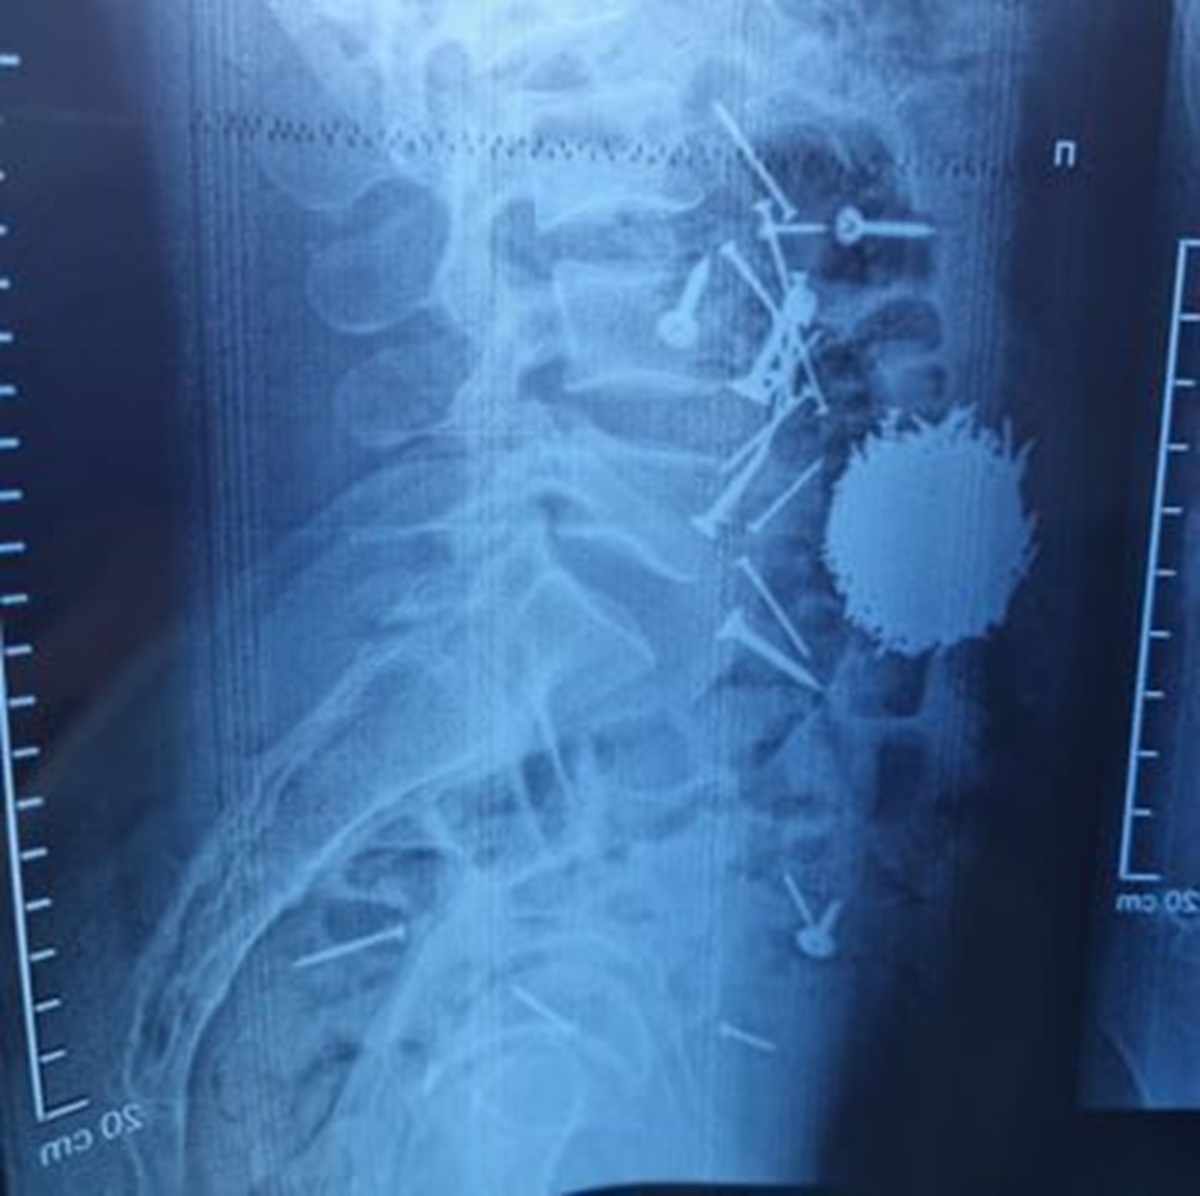

Молодой человек поступил в больницу с жалобами на сильную боль в животе. После проведения диагностических процедур медики были поражены: рентгеновские снимки показали наличие в желудке большого количества металлических предметов.